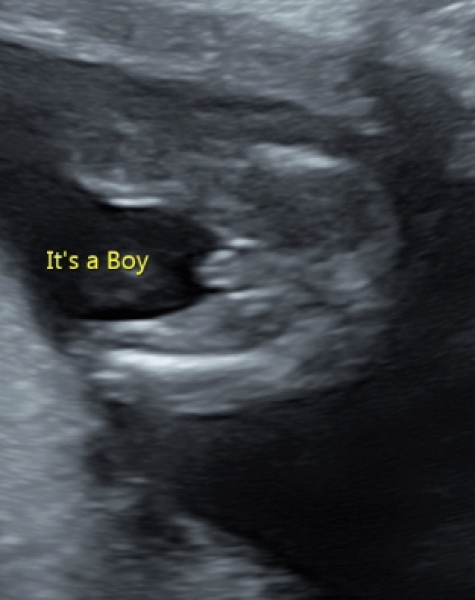

Hi all, I’m 16+ 4 today and had a private gender reveal scan a few days ago. I’m a bit confused with the scan pic. They say it’s a boy which I can understand as I see ‘sticky out bits’ 😂, however, I also see the 3 white lines when it’s a girl, the ‘hamburger’ shape. I have both boys and a girl already but never been undecided with my scans. Do you think it’s the correct prediction of a boy? X